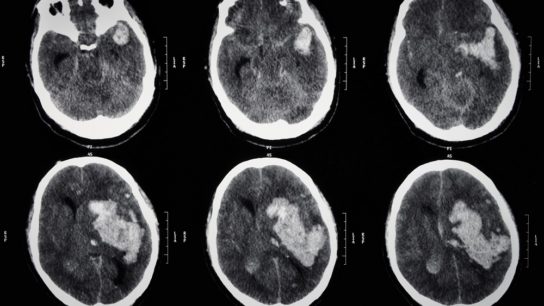

The use of guideline recommendations from the IDSA for neuroimaging in the management of community-acquired bacterial meningitis is most likely to lead to detection of major head CT scan findings that subsequently affect clinical management.